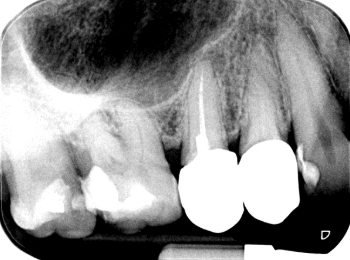

Röntgen Langzeitprovisorium

15: Zustand mit Langzeitprovisorium nach Ausheilung nach Revision.